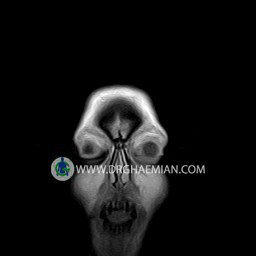

پزشکان اغلب از تصویربرداری ام آر آی برای تشخیص و درمان عارضه های پزشکی که فقط با استفاده از اشعه ایکس یا میدان مغناطیسی و امواج رادیویی قابل مشاهده است، استفاده می کنند. دستگاه ام آر آی تصاویر دقیق از ساختار های داخلی بدن ایجاد می کند. در این کیس نوریت اوربیت چب و سلای خالی بیمار مشاهده می شود.

ORBIT MRI

(with and without contrast)

Technique:Axial T1 , Axial , sagittal , coronal FSE T2 , coronal T1, sagittal fat sat T2 , Axial , sagittal T1 post Gd .

The both orbit are symmetrical and of normal size , with normal development of the orbital cones .

The bony orbital walls show a normal configuration with smooth and, sharp margins .

No foci of bone destruction , no circumscribed expansion of the bony or soft – tissue components of the orbital are evident .

The globes are symmetrical and of normal size and the ocular contents show normal signal characteristics .

The ocular walls are smooth , sharply defined , and of normal thickness .

The retrobulbar fat, ophthalmic vein and lacrimal apparatus are unremarkable .

Evaluable portions of the neurocranium and paranasal sinuses show no abnormalities .

No seen any evidence of ocular herniation

– Small fluid around the left optic nerve with mild edema suggestive for left optic neuritis

– Extension of suprasella cistern to sella with thin pituitary gland in floor of sella ( empty sella )

are seen

REPORTED BY :Dr DrNaser. Ghaemian.